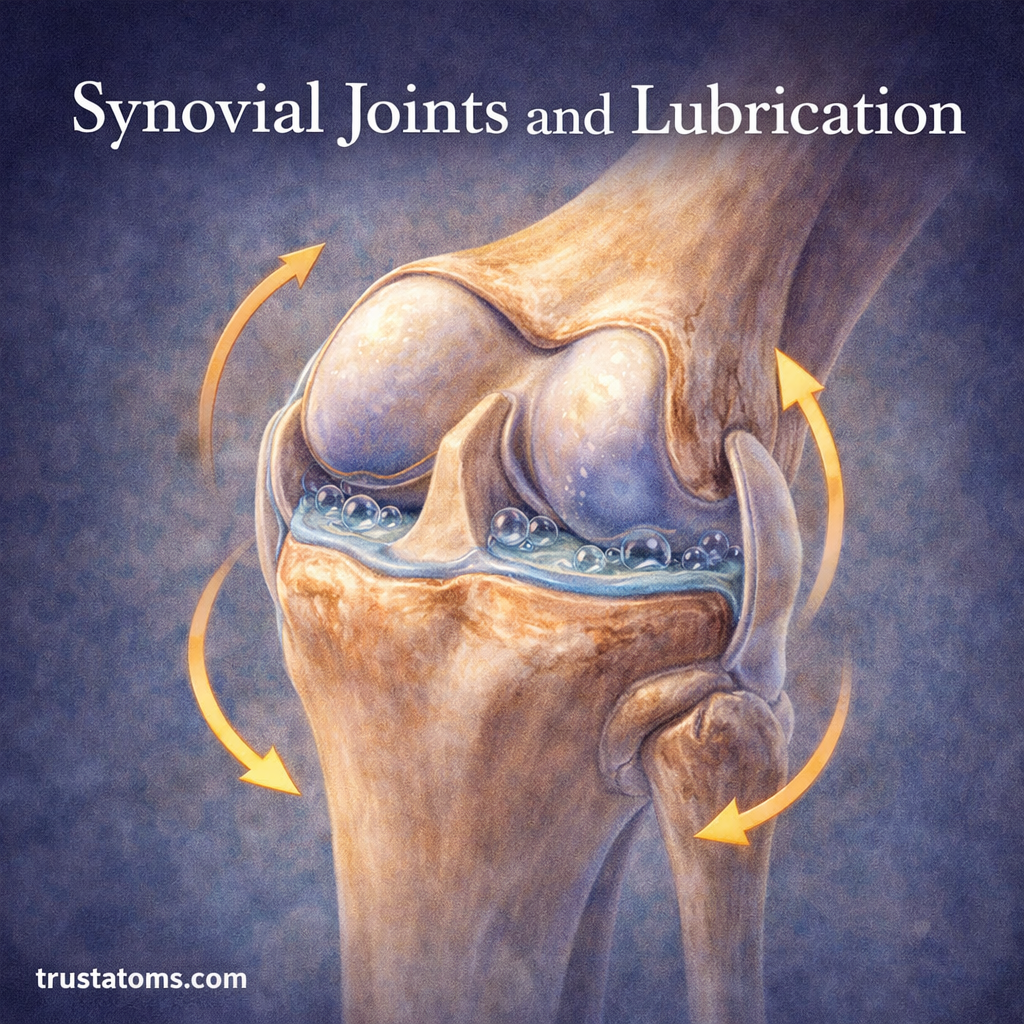

Structure of a Synovial Joint

Each part of a synovial joint has a specific role in reducing friction and maintaining joint integrity.

Articular Cartilage

- Smooth, slippery tissue covering bone ends

- Reduces friction during movement

- Absorbs shock

Synovial Membrane

- Inner lining of the joint capsule

- Produces synovial fluid

Joint Capsule

- Tough outer layer that encloses the joint

- Provides stability and protection

Synovial Fluid

- Thick, viscous fluid inside the joint cavity

- Acts as a lubricant and nutrient carrier

How It Works

When a joint moves:

- Synovial fluid spreads across cartilage surfaces

- It forms a thin, slippery film

- This minimizes direct contact between bones

This process allows joints to move with minimal resistance.